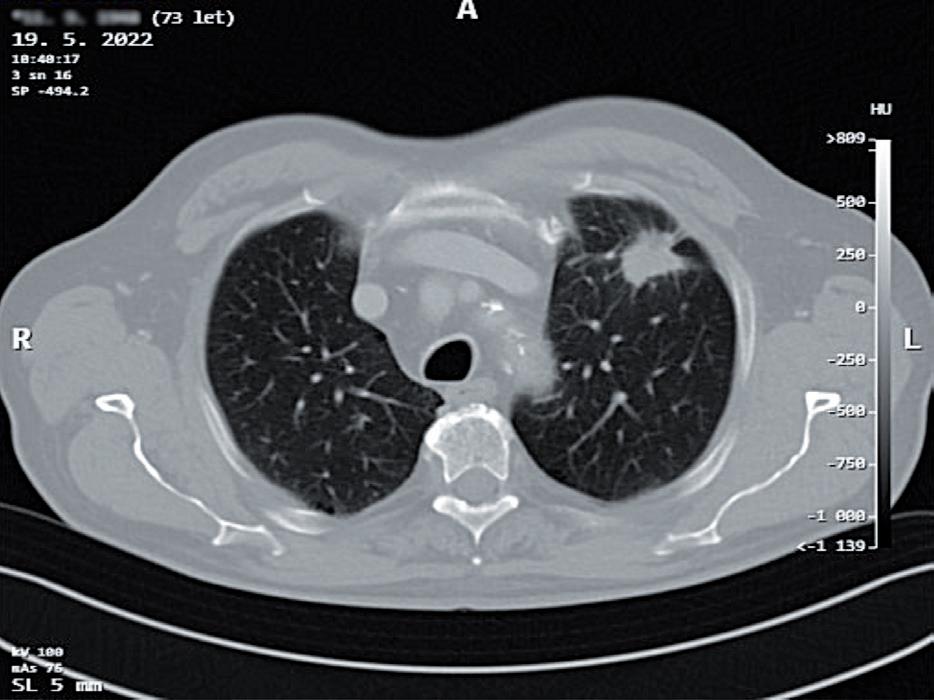

obr. 3.3 Nádory anatomicky vhodné pro videotorakoskopické nebo videorobotické operační řešení; a) potvrzený 2,5cm nemalobuněčný plicní karci nom v S3 levé plíce u 73letého muže, b) endobronchiální karcinoid středního lobárního bronchu u 68leté ženy

Pokud musíme uvažovat o minitorakotomii, jsou pro videotorakoskopickou plicní resekci ideální nádory o velikosti do 5 cm (obr. 3.3). Tedy malignity o klasi fikaci do T2b tumoru dle 8. vydání TNM klasifikace v české verzi z roku 2018 [33] . Minitorakotomií lze odstranit i nádory a nenádorové infiltrace větší, než je rozměr kožního řezu minitorakotomie [34]. Stlačitelnost a elasticita tkáně postižené nádorem je velmi malá. Prů chodnost nádoru minitorakotomií se odvíjí od rozměrů nejmenšího příčného průřezu afekce. Nejmenší příčný průměr kombinace nádoru s případným zánětlivým in filtrátem v okolí by neměl přesahovat rozměry minito rakotomie.

uzlinách. Indikující chirurg je však často v situaci, kdy se primární ložisko v plíci podezřelé z maligního původu nezdařilo verifikovat bronchoskopií s biopsií nebo kar táčkovou cytologií, ani punkční transparietální biopsií pod CT (obr. 3.9, 3.10).